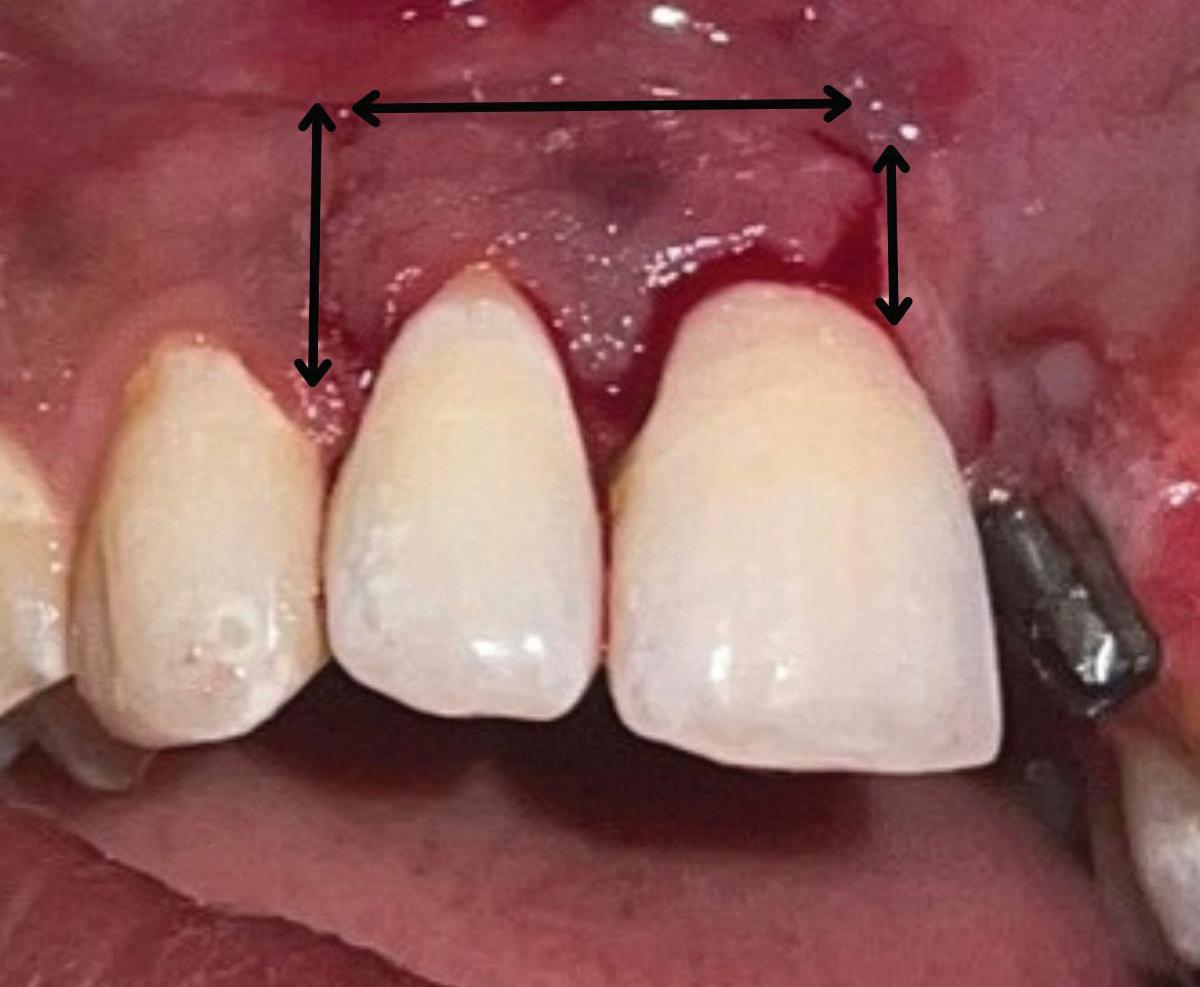

In the endodontic stage, conservative endodontic preparation and obturation with modern techniques are performed as they are for any tooth. All endodontic procedures are performed under an operating microscope to maximize visualization and illumination of the fracture line (Fig 1). The coronal portion of the newly placed gutta percha is removed 2 to 3 mm below the deepest extent of the crack in the affected canal to prepare for intraradicular barrier placement (Fig 2). Gutta percha is also removed 2 to 3 mm into the other noncracked canal orifices in the tooth to prepare for traditional orifice barriers. Microscopic transillumination with a fiber-optic light, in which an LED light probe is placed against buccal or lingual tissues overlying the roots, is utilized to illuminate the root and enhance visualization of the crack (Fig 3). A flowable resin-modified glassionomer or composite resin is then placed in this newly created void from the level of the gutta percha to the floor of the pulp chamber in all canal orifices (Fig 4). A composite resin core is then placed to permanently restore the endodontic access. If a temporary or permanent crown is not placed immediately after the endodontic procedures, the tooth is reduced

These CAIPP lesions are best identified and monitored with high-resolution CBCT scans (Fig 5). However, even advanced CBCT systems, with voxel sizes as small as 0.075 mm, are not capable of reliably detecting cracks, which are typically much narrower.45 Therefore, the presence of a CAIPP defect, combined with careful clinical diagnostics and evaluation, remains the most reliable indirect indicator of a crack with radicular extension.

The presumed clinical significance of a lingering CAIPP defect is that the persistent biofilm in the crack can lead to further periodontal breakdown and symptoms. However, the changes in these areas were monitored over the course of

previous studies, and these bony lesions did not progress over time and remained asymptomatic.4,26 Together, these studies demonstrated that the persistent bony defect adjacent to the cracks may remain stable and asymptomatic over time, making saving teeth with this technique a realistic option for patients.

Fig 5. CBCT images of a crack-associated isolated periodontal pocketing defect associated with a distal crack in the mandibular right first molar. A. Sagittal view showing angular crestal bone loss (arrow) along a distal radicular crack at the cervical margin. B. CBCT 3-dimensional rendering showing the defect (arrow) at the distal root. C. Axial view showing the defect (arrow) at the distal root.